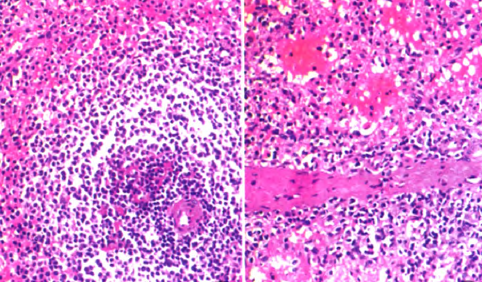

诊断:盆腔肿物,性质待查 治疗:行子宫全切除术。术后子宫性病理活检,子宫做多个切面,在肌层内查见2个大小不等灰白色肌瘤,肌瘤面积0.3cm×0.2cm—1cm×0.6 cm,肌瘤切面质韧,灰白色,呈编织状,边界清;内膜光滑,厚0.2—0.3 cm,肌层厚2.5—3.5 cm,部分呈海绵状,子宫颈光滑,切面质韧,质地较细。盆腔内不规则肿物1个,灰红色,表面结节状,11cm×7.5 cm×3.5 cm大小,做多个切面,切面见多个结节,结节面积:0.4 cm×0.3 cm~4.3 cm×2.5cm,结节切面质脆,灰红色,质地细,结节边界清。另送圆形结节5个,直径1~3 cm不等,切面性质同盆腔较大肿物,均有包膜。 镜检:患者子宫检查为子宫肌瘤,子宫腺肌病,病变无特殊性。盆腔多个肿物病变性质基本一致,为扩张血窦样组织,窦腔内充满红细胞,似脾红髓淤血,在血窦样组织间有大小不等、发育良莠不齐的白髓样结节,结节较大者有小中央动脉,结节较小者中央动脉不明显,内皮细胞无异型性,细胞分化均无异型性,无病理性分裂象。可见玻璃变性纤维结缔组织似脾小梁样结构。